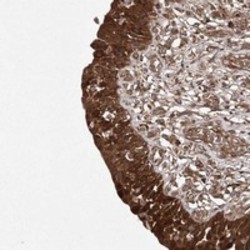

- Immunohistochemical staining of human urinary bladder with TMEM9B polyclonal antibody (Cat # PAB23164) shows strong cytoplasmic positivity in urothelial cells at 1:10-1:20 dilution.

- Immunohistochemistry (Formalin/PFA-fixed paraffin-embedded sections)